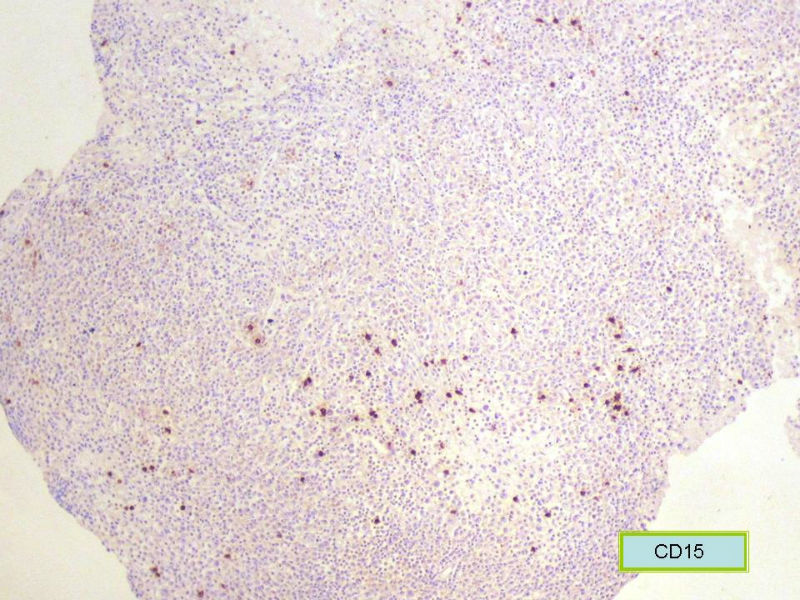

该患者可能存在病毒的感染,抑或是EB病毒的感染,包括CD30+的细胞在内,夹杂在组织细胞、小淋巴细胞之间的一些个大细胞是活化的淋巴细胞,表型看来属B细胞。整个形态呈反应性增生的形态。

总之,现有的图片显示的形态和IHC标记尚不足以诊断为淋巴瘤,除非有有基因重排的支持。

请看下图,显示的细胞比较杂,胞浆较丰富,胞核没有什么特别的异型性。没有促纤维增生反应和围血管生长表现,没有肿瘤性坏死,没有见到更多的核分裂,特别是病理性核分裂。因此认为,本例是淋巴组织反应性增生,可能是对病毒感染的反应。